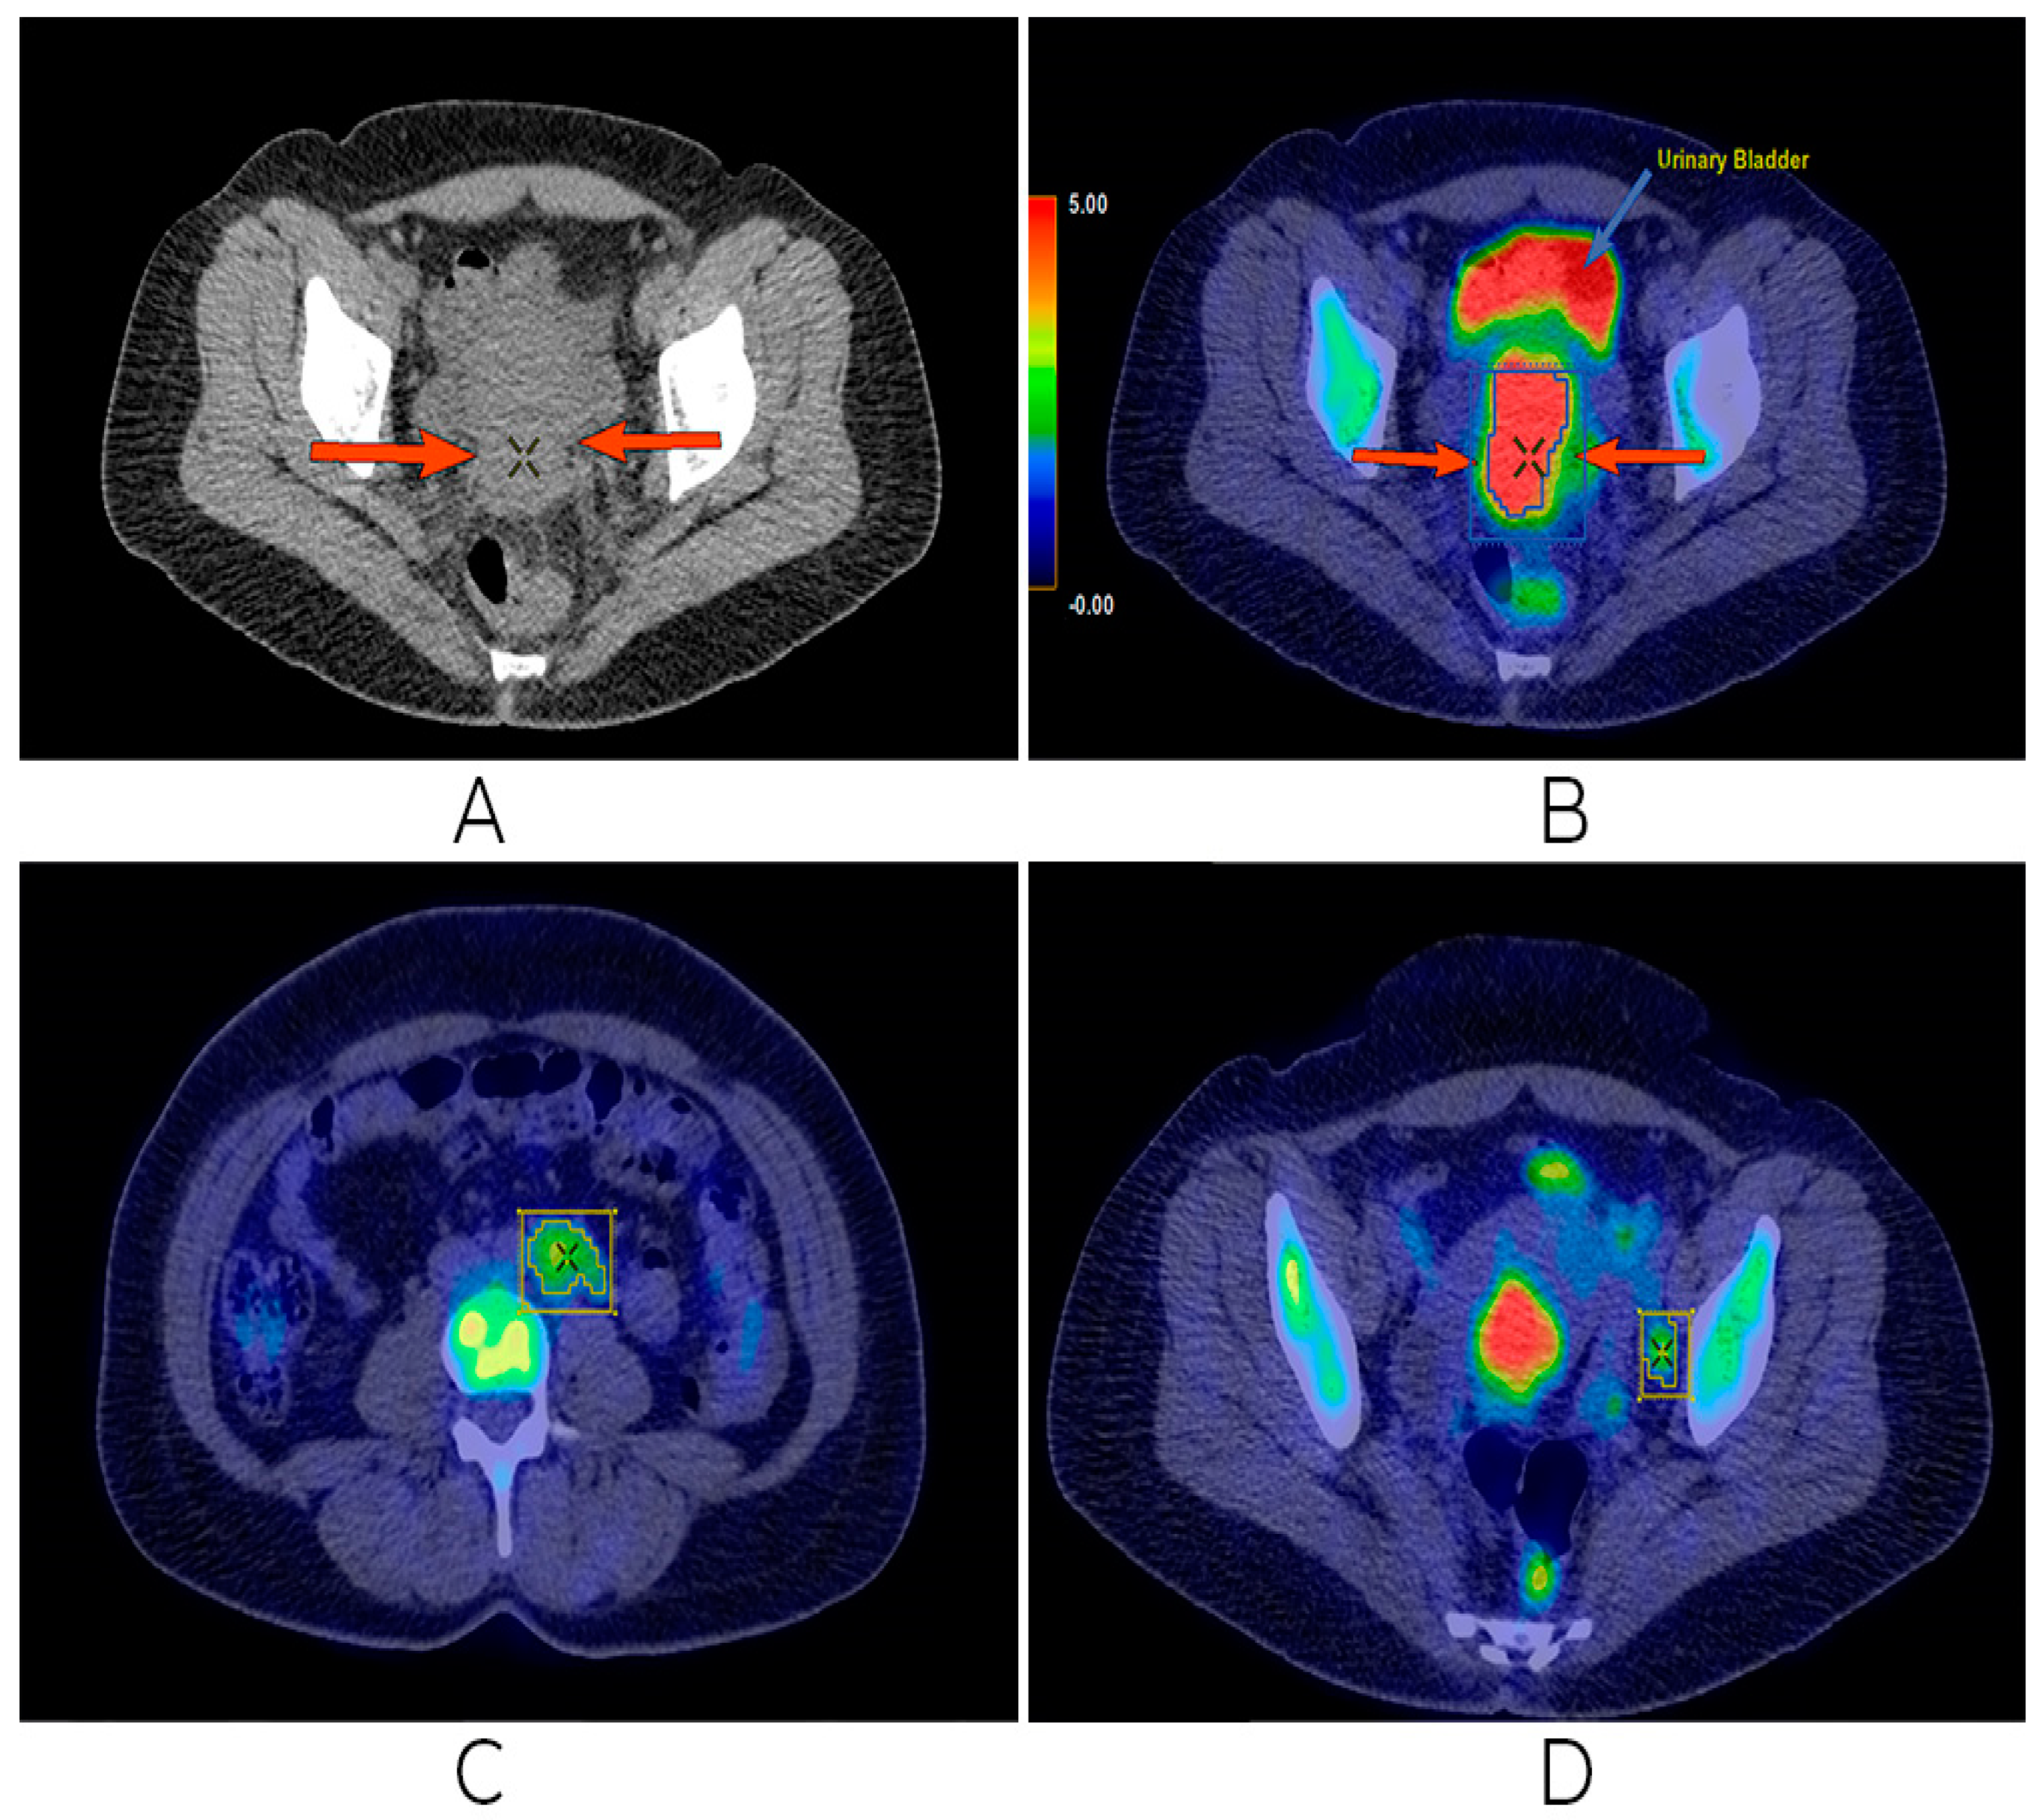

PET-CT画像診断マニュアル fmed-09-896494-g001.jpgの詳細情報

fmed-09-896494-g001.jpg。The PET/CT Systems Market to Gel Well with Technological。PET CT Imaging with FDG in the Therapeutical Management of。 現在、1名がこの商品を検討中です

PET-CT画像診断マニュアル

中外医学社

2008/04/01

■ISBN10■

4498013549

■ISBN13■

9784498013544

■コンディションランク■

良い

コンディションランク説明

ほぼ新品:未使用に近い状態の商品

非常に良い:傷や汚れが少なくきれいな状態の商品

良い:多少の傷や汚れがあるが、概ね良好な状態の商品(中古品として並の状態の商品)

可:傷や汚れが目立つものの、使用には問題ない状態の商品

■コンディション詳細■

書き込みありません。水濡れ防止梱包の上、迅速丁寧に発送させていただきます。

PET-CT画像診断マニュアル

中外医学社

2008/04/01

■ISBN10■

4498013549

■ISBN13■

9784498013544

■コンディションランク■

良い

コンディションランク説明

ほぼ新品:未使用に近い状態の商品

非常に良い:傷や汚れが少なくきれいな状態の商品

良い:多少の傷や汚れがあるが、概ね良好な状態の商品(中古品として並の状態の商品)

可:傷や汚れが目立つものの、使用には問題ない状態の商品

■コンディション詳細■

書き込みありません。水濡れ防止梱包の上、迅速丁寧に発送させていただきます。